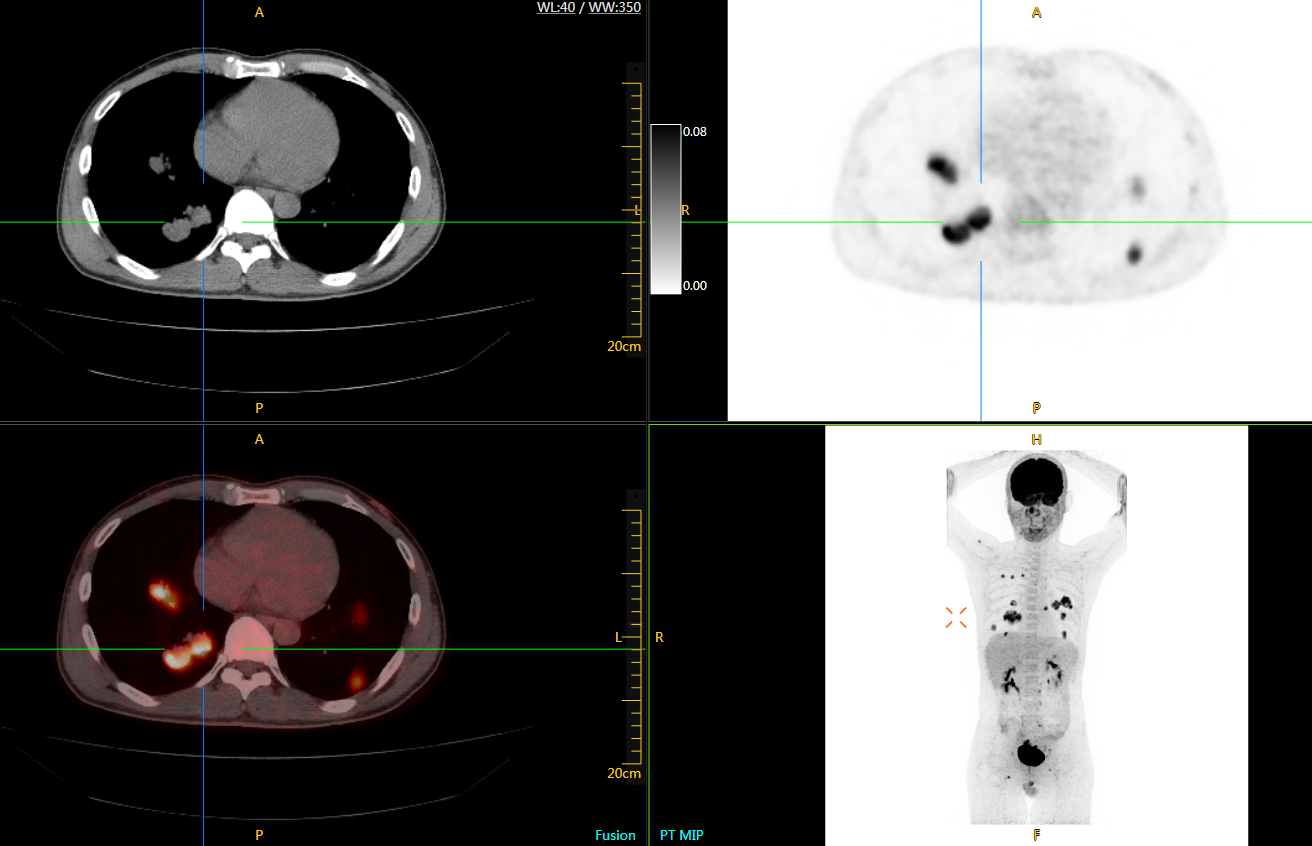

uExplorer探索者不再局限于傳統(tǒng)靜態(tài)代謝過(guò)程3D成像,而是在此基礎(chǔ)上新增一個(gè)維度——時(shí)間,從而實(shí)現(xiàn)4D全景成像。

注射總劑量為7.8mCi,14分鐘全身采集時(shí)間,在擁有超高靈敏度與超高分辨率的uEXPLORER上,即可得到展示顯示人體諸多精細(xì)結(jié)構(gòu)的高清三維圖像。

注射總劑量為7.8mCi,注射后1.6小時(shí),基于uEXPLORER探索者掃描1分鐘的圖像